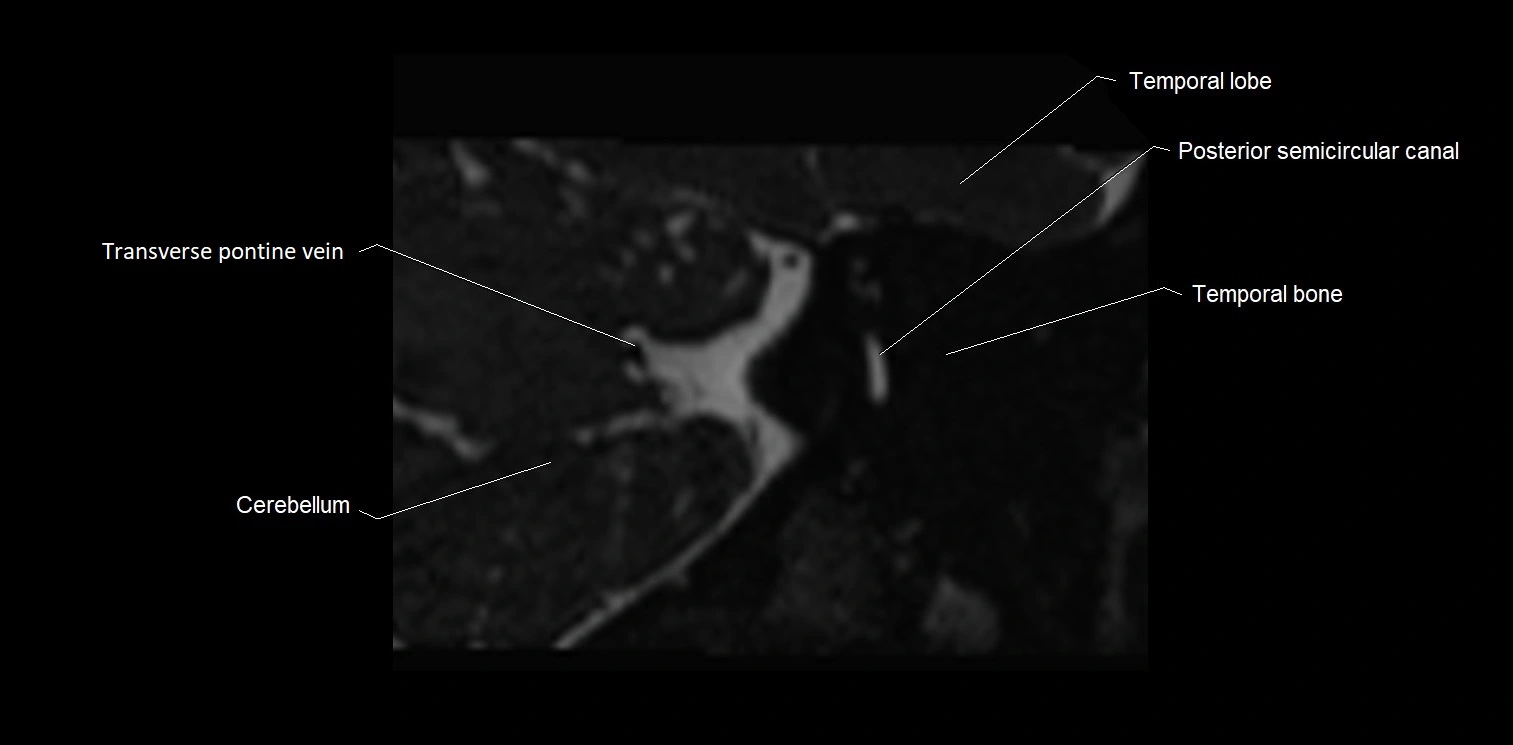

image

MRI images